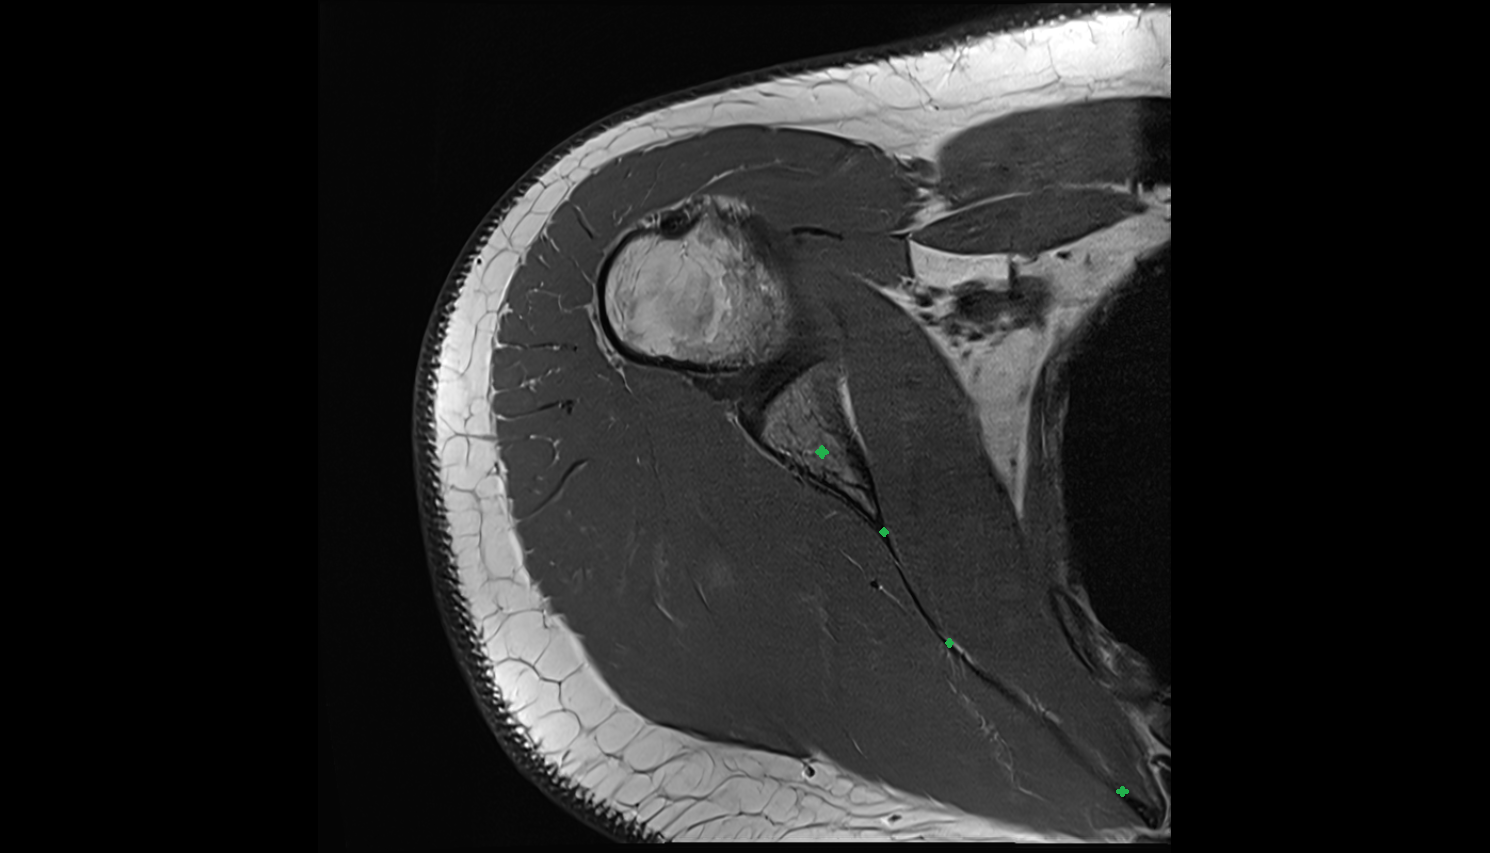

- Shoulder joint (glenohumeral joint)